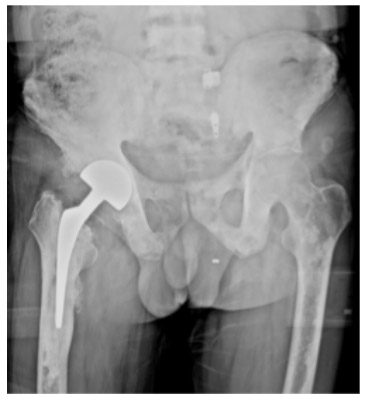

CASE 25: Fracture due to prostate cancer metastasis to the right hip (femoral neck).

Post-surgery: The X-ray shows a partial (cemented) hip replacement.